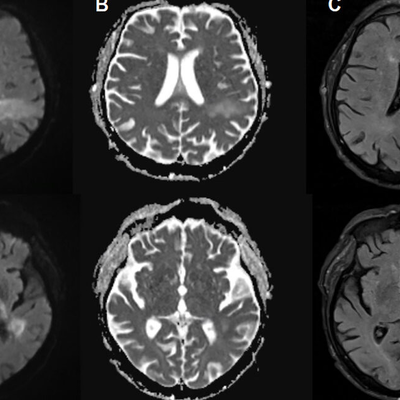

The first person in the world to be treated with this futuristic material, Res-Q-Foam, has died at 86. A social experiment in which payphones were placed at a Nevada senior home and a Boston University coffee shop were used to connect with strangers. K-pop group BTS has made their comeback with their album "Arirang", following a four-year hiatus. The latest episode of "The Bachelorette" has been cancelled following a video by TMZ showing Taylor Frankie Paul throwing objects at her former boyfriend.